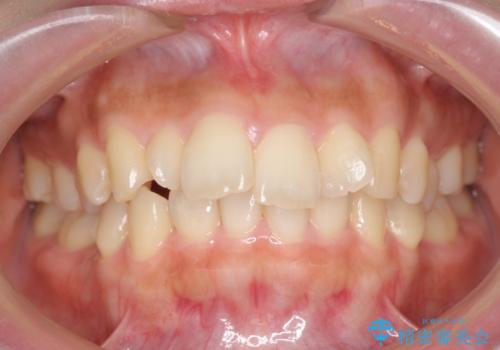

下顎がとても小さく後方位であるため、オトガイの閉口時のシワは完全になくすことは難しかったですが、前歯も大きく下がり満足していただきました。

矯正治療は審美的な側面を持っておりますが、小さすぎる下の顎に口元を無理やりあわせるのも、歯の移動量が大きすぎて適切な治療とは言えないと思います。健康を損なう美容整形とは違うからです。前歯については、適度に下げる量をコントロールすることも大事です。